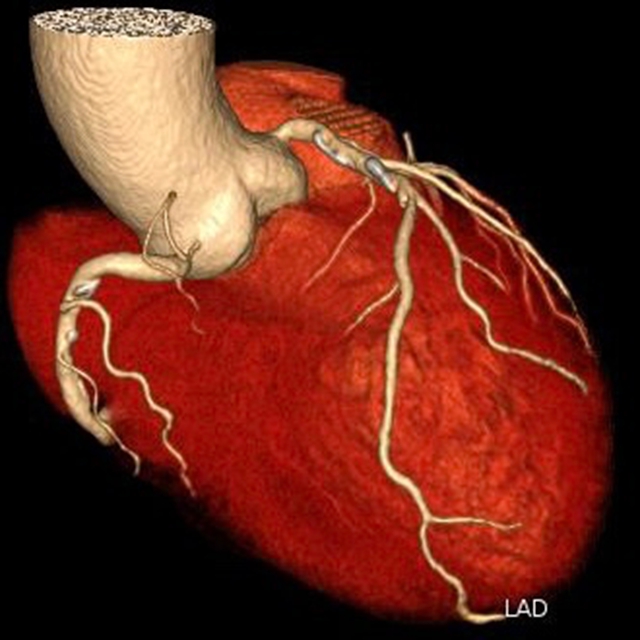

“一站式”CT检查

胸痛三联征“一站式”CT检查是指通过一次扫描、一次注射造影剂可同时显示冠状动脉、肺动脉及主动脉三种血管的图像,有助于早期、快速诊断,同时可以最大程度降低辐射剂量。因此已成为目前评估急性胸痛患者的首选检查方法。

1.急性心肌梗死的诊断:“一站式”CT检查可以快速识别冠状动脉的狭窄或堵塞程度,及时帮助医生确认诊断,制定进一步的治疗方案。